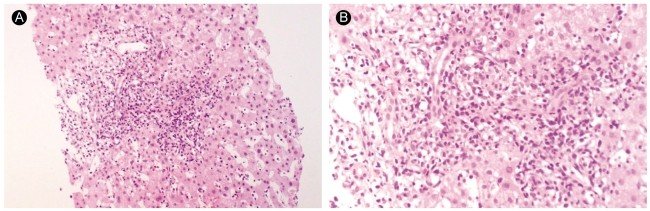

On hospital day 7, her course was complicated by several episodes of fever with negative blood cultures. Serologic and virologic studies revealed the absence of hepatitis B surface antigen, hepatitis B core antibody IgM, hepatitis C antibody, and negative CMV, but positive for hepatitis A virus antibody IgM and EBV VCA IgM, EBV VCA IgG was positive and Epstein-Barr nuclear antigen (EBNA) IgG was negative. The neck node biopsy revealed reactive hyperplasia with inflammation. The liver biopsy revealed dense mononuclear cell infiltration, indicating activated lymphocytes in the portal tract. The hepatic lobular architecture was generally preserved and the lobule showed sinusoidal lymphocytic infiltration, individual hepatocyte degeneration and few spotty necrosis. Portoportal extension due to inflammatory activity and fibrosis was also observed (Fig. 3).

Figure 3.

Liver biopsy findings of case 2. The lobule exhibits sinusoidal lymphocytic infiltration, individual hepatocyte degeneration, and few spotty necroses. Some of the portal tract shows dense mononuclear cell infiltration, indicating activated lymphocytes (A: H&E, ×100, B: H&E, ×200).